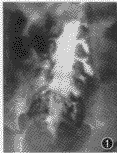

影像学检查:(1)脊髓造影(MG)所见:造影柱于L1椎体下缘处完全性阻塞,阻塞端肿瘤轮廓显示欠清,推挤蛛网膜下腔及脊髓向左后方移位,脊髓两侧蛛网膜下腔均受压狭窄,病变侧蛛网膜下腔与椎弓根内缘距离7 mm,邻近根囊消失,T9~L2椎体及附件均未见骨质破坏(图1,2)。(2)脊髓造影CT扫描(CTM)所见:L1水平椎管内硬膜外右侧方可见略高密度软组织肿块,肿块边界欠清楚,CT值45 HU,压迫硬膜囊、蛛网膜下腔及脊髓,使之变形并向左后移位,L1 椎体及附件未见骨质破坏和吸收(图3)。影像学诊断:椎管内硬膜外(T9~L2)占位性病变。

图1 造影柱于L1下缘处完全性阻塞;阻塞端肿瘤轮廓显示欠清,推挤蛛网膜下腔及脊髓向左后方移位,脊髓两侧蛛网膜下腔均受压狭窄,病变侧蛛网膜下腔与椎弓根内缘距离7 mm,邻近根囊消失,T9~L2椎体及附件均未见骨质破坏